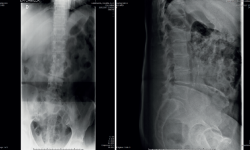

• Resonancia magnética (RM) lumbar (Figura 2): sagitales con secuencias T2 y STIR. Espondilodiscitis aguda con absceso en canal raquídeo y prevertebral.

Figura 2. Resonancia magnética sagital T2 y STIR.